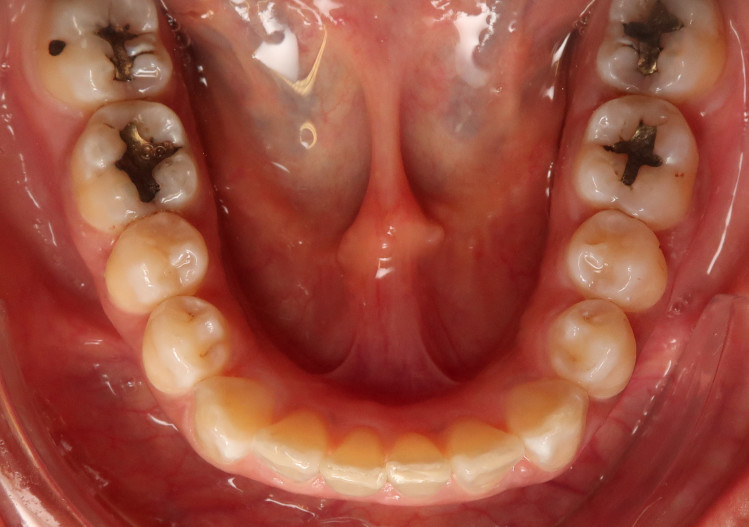

Die FRS-Auswertung (Abb. 1d) ergab eine distal-basale Kieferrelation nach WITS (2,6 mm) bei tendenzieller maxillärer Prognathie (SNA 86,5°). Aus der dentalen Analyse des FRS ging eine deutliche Anteinklination der Oberkieferinzisivi (IOK-NL 126,5°) und eine manifeste Anteinklination der Unterkieferinzisivi (IUK-ML 103,6°) bei stark verkleinertem Interinzisalwinkel (IOK-IUK 112,3°) hervor. Die vertikalen Parameter ergaben einen brachiofazialen Gesichtsschädelaufbau. Die Auswertung des OPG (Abb. 1e) zeigte eine adulte Dentition mit fehlenden dritten Molaren. Außerdem war eine extreme Mesialkrümmung der Wurzel 25 erkennbar. Es zeigte sich ein moderater generalisierter horizontaler Knochenabbau des Limbus alveolaris im Ober- und Unterkiefer von ca. 15 Prozent.

Der intraorale Befund (Abb. 2a–e) sowie die Modellanalyse (Abb. 3a–e) zeigten neben dem Diastema mediale im Oberkiefer vor allen Dingen eine Anteinklination und Supraokklusion beider Fronten. Besonders anterior wiesen beide Zahnbögen eine transversale Enge auf. Dies zeigte sich in einem deutlichen Unterkieferfrontengstand mit Labialkippung des Zahnes 41. Neben Abrasionen und Schlifffacetten, vor allem in der Front, waren auch vereinzelt Gingivarezessionen erkennbar. An Zahn 11 lag eine Schmelzfraktur der Inzisalkante vor. Durch die zwangsgeführte Laterognathie ergab sich eine Mittellinienverschiebung nach rechts von 3 mm. Eine beidseitige Distalokklusion bei vergrößerter sagittaler (6 mm) und vertikaler (5 mm) Stufe war erkennbar. Aufgrund der deutlichen transversalen Zahnbogenenge im Unterkiefer ergab sich links eine Tendenz zum Scherenbiss.